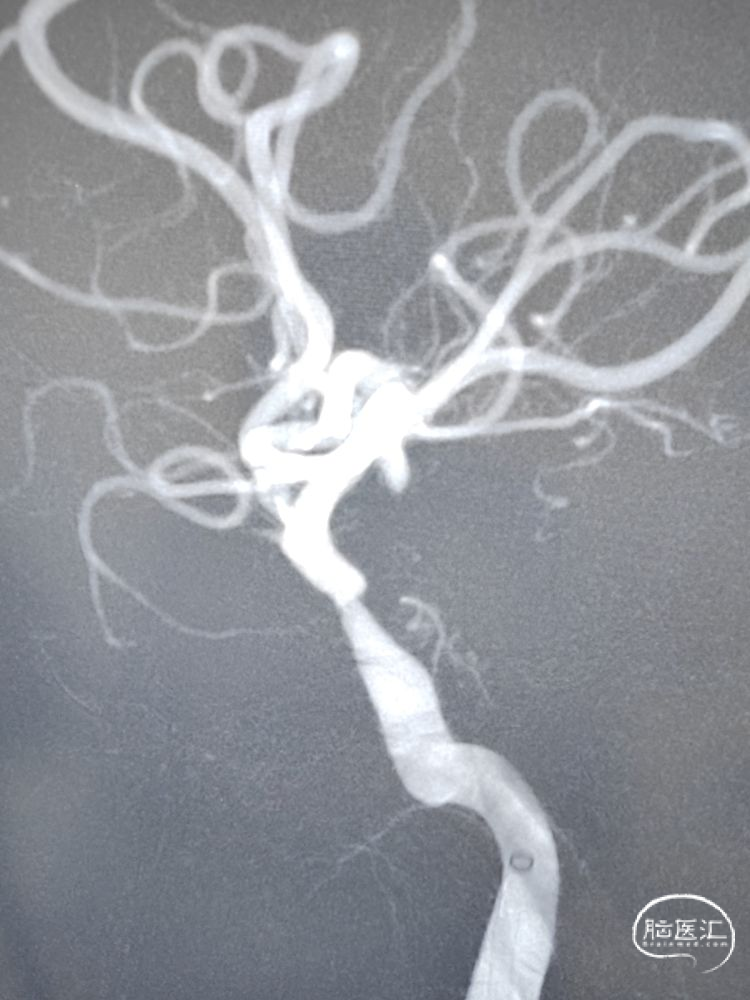

支架到位及释放:

在颅内支撑导管的支持下,沿微导丝将4.0mm*13mm Bridge椎动脉雷帕霉素靶向洗脱支架送至狭窄部位,支架到位比较顺利,通过狭窄处支架略有卡顿、微导丝有些回退,支架近端定位在接近正常段管径4mm处,略高于额定压扩张球囊释放支架,球囊缓慢泄张后造影提示支架内血流通畅,支架完全张开贴壁,局部无残留狭窄。